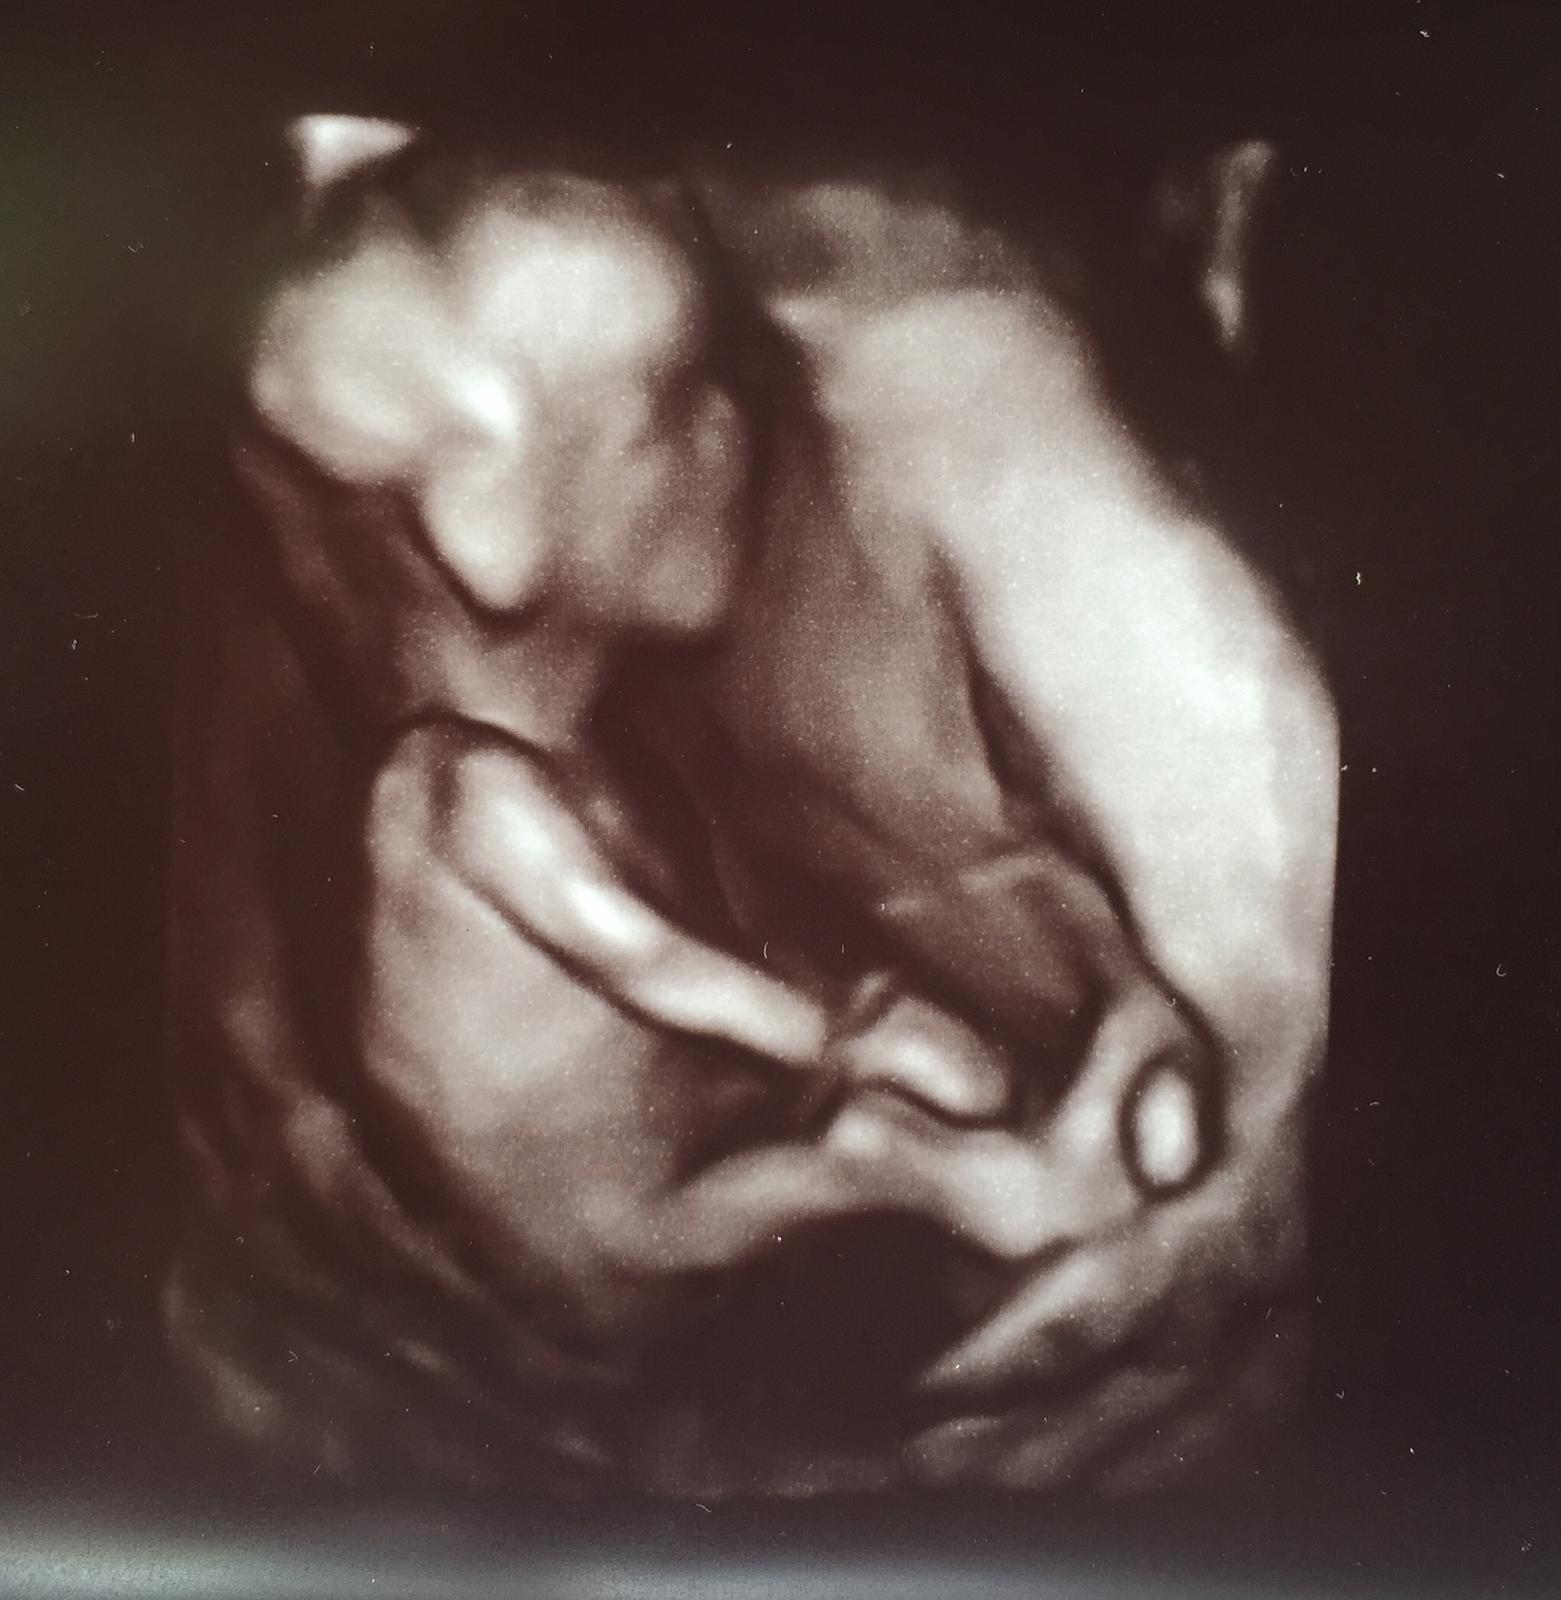

@xenabojovnica kraaasna fotecka 😍 my ideme o tyzden a uz sa tesiiiim, pevne verim a dufam ze bude vsetko v poriadku 😊